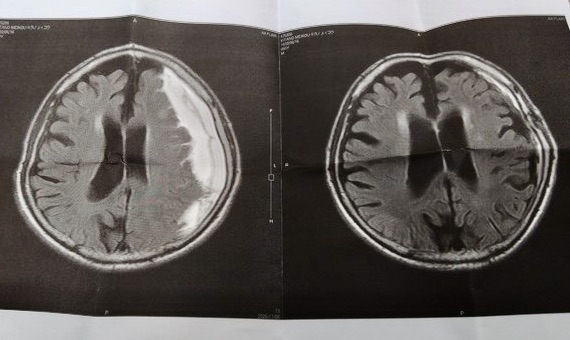

医師の話では、右脳に出来ていた血腫は、ほとんどなくなっていて、脳のシワも回復しているそうで・・「お土産です」と、最後にコピーをくれました。

う〜〜ん、左側は11月8日、手術前の状態で、確かに、手術して良かったな〜 なんですが、8月に頭を打ったのは左なのに、右側に血腫が出来ていた次第で、